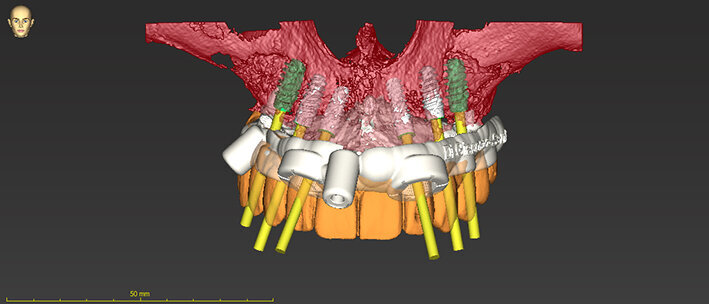

Grazie al flusso digitale, possiamo inserie nel software anche il file STL del provvisorio pre-chirurgico preparato e quindi progettare il provvisorio immediato (Fig. 41). La pianificazione degli impianti a questo punto viene effettuata in modo protesicamente guidato ed è facile posizionare correttamente l’impianto e verificarlo nelle cross del software. Si progetta e si disegna quindi la dima chirurgica (Fig. 42). Il giorno dell’intervento abbiamo già tutto pronto e la paziente presenta uno stato di salute dei tessuti ottimale grazie anche al fatto che ha potuto portare per tutto il periodo una protesi fissa.

Procediamo quindi all’inserimento di sei impianti BLX Straumann (Straumann Group) (Fig. 43, 44), ed utilizziamo gli impianti posizionati nella tuberosità per stabilizzare la dima chirurgica e il provvisorio sul modello master di lavoro digitale. La funzionalizzazione del provvisorio immediato subito dopo l’intervento viene effettuata con l’utilizzo della tecnica DIL19 (Figg. 45, 46).